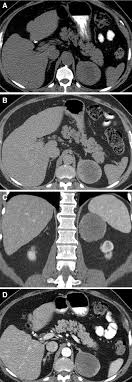

Optimal Diagnosis Of Adrenal Masses Sciencedirect

Optimal Diagnosis Of Adrenal Masses Sciencedirect from ars.els-cdn.com

The adrenal gland is involved by a range of neoplasms, including primary and metastatic malignant tumors; Usually, it is a small round mass. Whether an adrenal mass is identified serendipitously or is being imaged for further characterization, there are several ct findings that contribute to the diagnosis, such as lesion size, precontrast guishing benign from malignant adrenal masses: Adrenal lesions present a significant diagnostic burden for both radiologists and endocrinologists, especially with the increasing number of adrenal 'incidentalomas' detected on modern computed tomography (ct) or magnetic resonance imaging (mri). Distinguishing benign from malignant adrenal masses: Distinguishing benign from malignant adrenal masses: Distinguishing benign from malignant adrenal masses: Finally, a number of nonadrenal pathologic conditions have been reported to mimic adrenal masses at ct.

Ct image of another adrenal mass mainly composed of macroscopic fat. A key objective is the reliable distinction of. Prior imaging if available) and cancer history. Population covered by the guidance. Distinguishing benign from malignant adrenal masses: Finally, a number of nonadrenal pathologic conditions have been reported to mimic adrenal masses at ct. Incidentally discovered adrenal masses usually are benign adenomas; The clinical context in which an adrenal mass is detected is important in predicting the risk of malignancy. Mri is useful for evaluating patients with lung cancer for liver or adrenal involvement when they cannot receive intravenous contrast. Adrenal masses <1 cm do not require further investigation. Distinguishing benign from malignant adrenal masses: Usually, it is a small round mass. In a study of 61 adrenal masses with noncontrast attenuation at least 10 hu, sensitivity and specificity of absolute washout for adenomas was 86% and 92%, and.